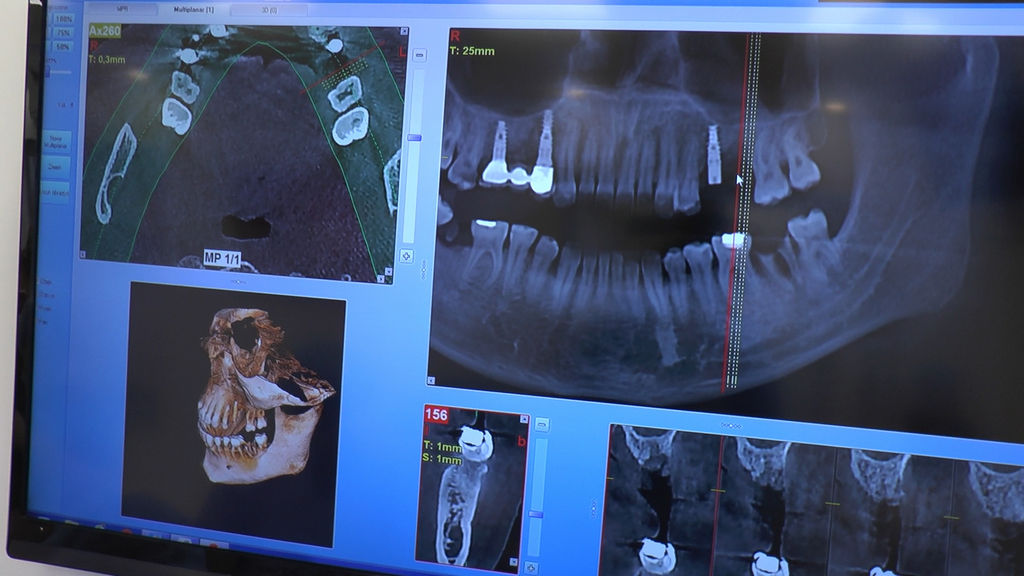

16 i 17 marca 2018 roku odbywa się VII Sesja Practiculum Implantologii Sezon V Grupa A. Jej motywem przewodnim jest chirurgia implantologiczna-kurs praktyczny z udziałem pacjentów. Lekarze wykonują procedury zabiegowe u pacjentów pod kierunkiem dr n.med. Violetty Szycik. W planie wszczepienie 34 implantów i zabiegi okołoimplantacyjne. Wszystkie zabiegi przeprowadzane są w bardzo trudnych warunkach, lecz lekarze zostali do nich doskonale przygotowani na wcześniejszych seminariach.  Fotogaleria przedstawia zabiegi wykonane drugiego dnia, w sobotę 17 marca 2018 roku.